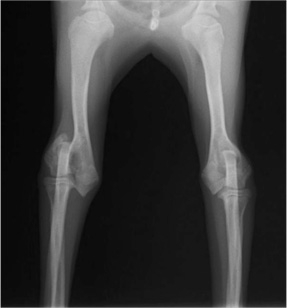

症例3:キルシュナーワイヤーのピンニングによる整復

ペルシャ猫 11ヶ月齢 雄

他院にて左大腿骨遠位の成長板骨折(salter-harrisⅠ型)が認められており、治療相談を目的として来院。当院にて、キルシュナーワイヤーを用いたピンニングにより骨折部位の整復を行いました。術後の経過は良好で、現在も経過観察中です。

術前レントゲン

術後レントゲン